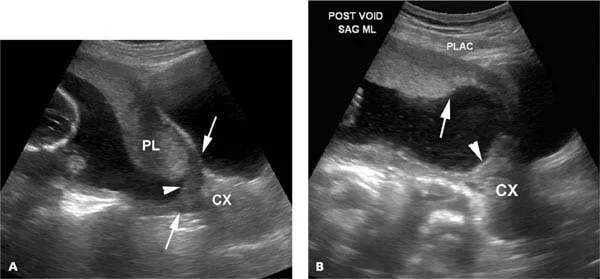

- Transvaginal ultrasound is the gold standard for diagnosis.

- Initial Test: Transabdominal ultrasound.

- Gold Standard: Transvaginal ultrasound (TVS) is safe & more accurate for precise localization.

- Follow-up: Repeat scan at ~32 weeks; many early previas resolve via "placental migration."